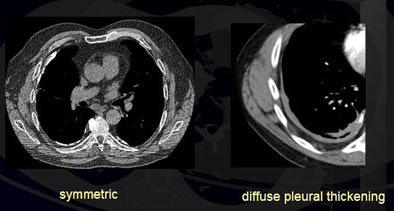

In all, 86% of the plaques were flat and 91% were symmetrical. More than 80% of pleural plaques "were completely flattened and inconspicuous, while 10% had these lobulated and rather thick nodules," Roberts noted.

Conversely, 14% of plaques were lobulated, 2% were asymmetric with a right-sided dominance, and 1% were associated with pleural effusions. Eleven percent of patients had diffuse pleural thickening.

| Researchers found that more than 86% of pleural plaques were completely flat and 91% were symmetrical. Eleven percent of patients had diffuse pleural thickening (top). Plaques that were asymmetrical in shape and mass-like were considered suspicious for malignancy (above). Plaques were detected in the lung fissures, mediastinum, diaphragm, and costal regions (below). All images courtesy of Dr. Heidi Roberts. |